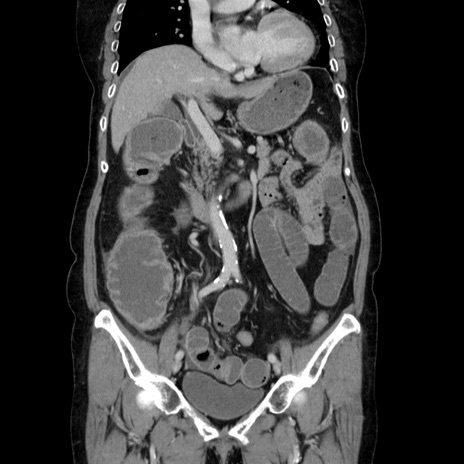

症例5(冠状断像)

【症例】70歳代女性

【主訴】お腹が張る

【現病歴】1週間くらい前から腹部膨満の自覚あり。昨日夜から増悪したため、本日救急外来受診。

【身体所見】意識清明、BT 36.5℃、BP 165/106mmHg、HR 80bpm、SpO2 98%、腹部:膨満、軟、自発痛・圧痛なし、触診にて不快感あり、腸蠕動音:減弱

【データ】WBC 12600、CRP 1.04